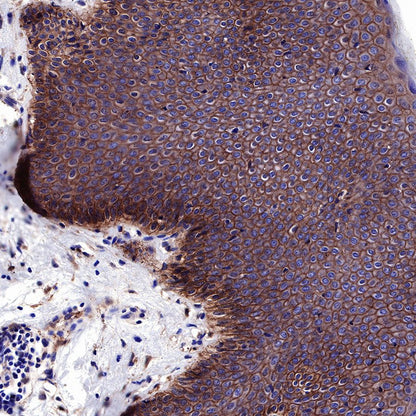

IHC shows positive staining in paraffin-embedded human esophagus. Anti-EGFR antibody was used at 1/2000 dilution, followed by a HRP Polymer for Mouse & Rabbit IgG (ready to use). Counterstained with hematoxylin. Heat mediated antigen retrieval with Tris/EDTA buffer pH9.0 was performed before commencing with IHC staining protocol.